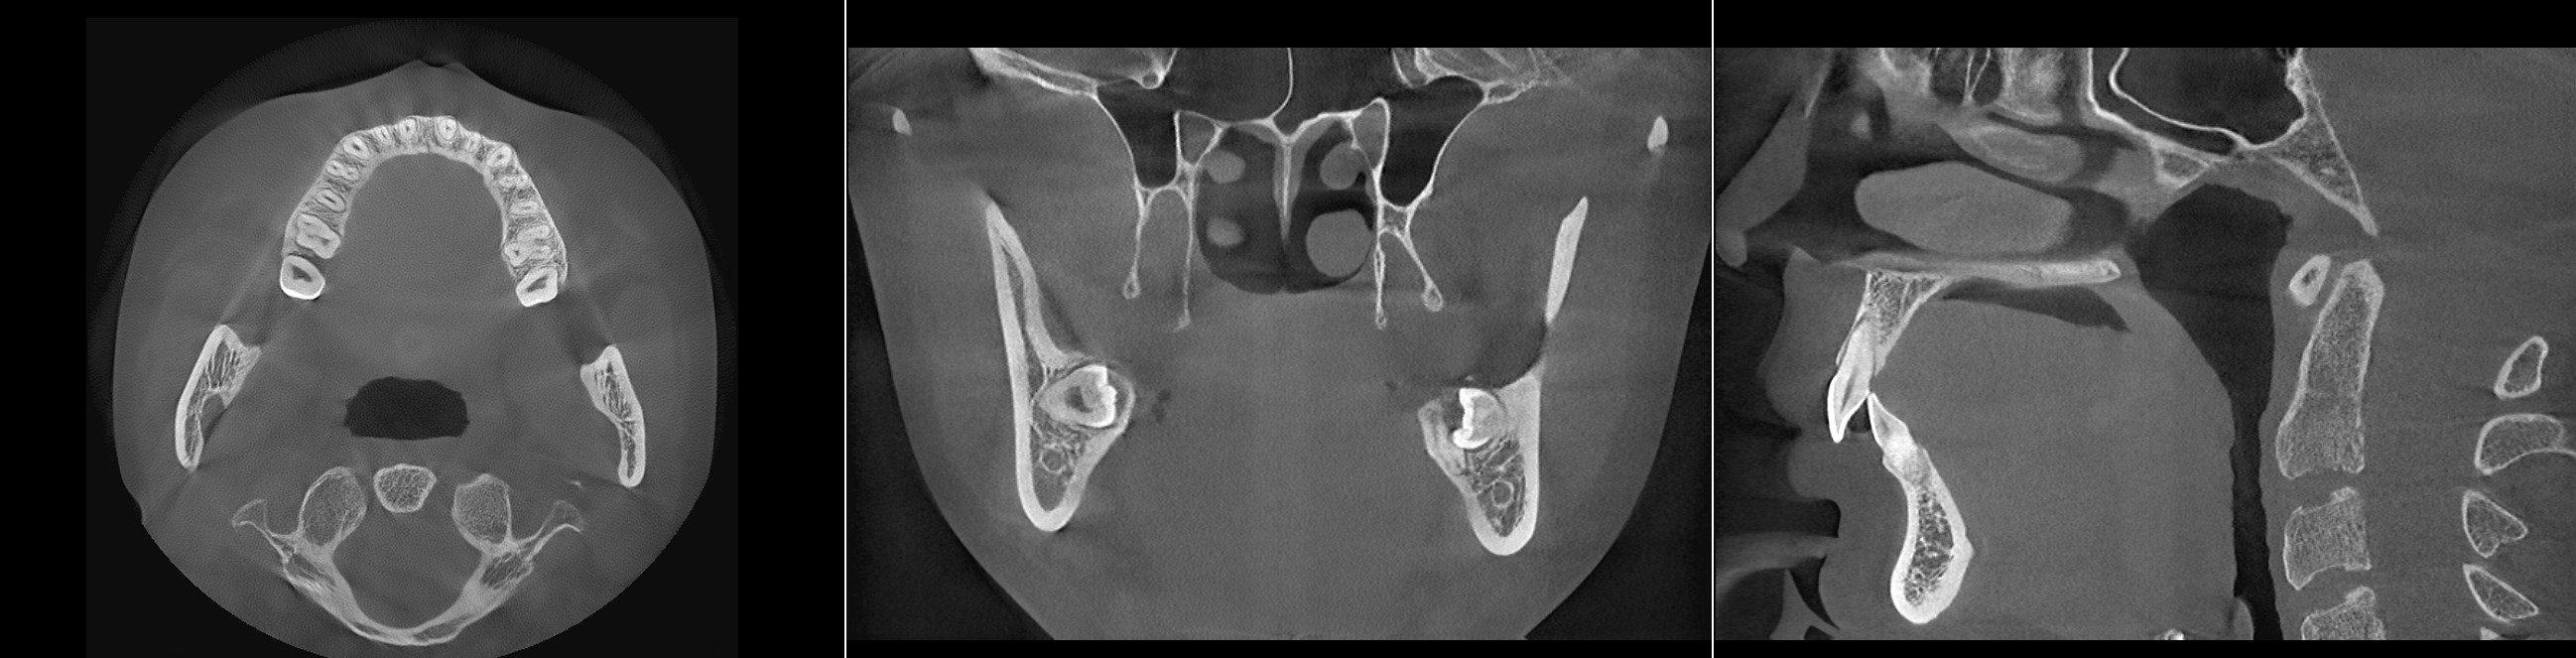

Split into parts

13